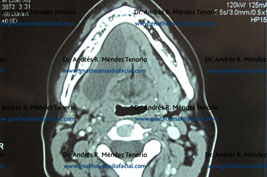

Tomografías computarizadas antes y después del procedimiento quirúrgico

Sialolito submandibular. El paciente presenta infección y edema en piso de boca